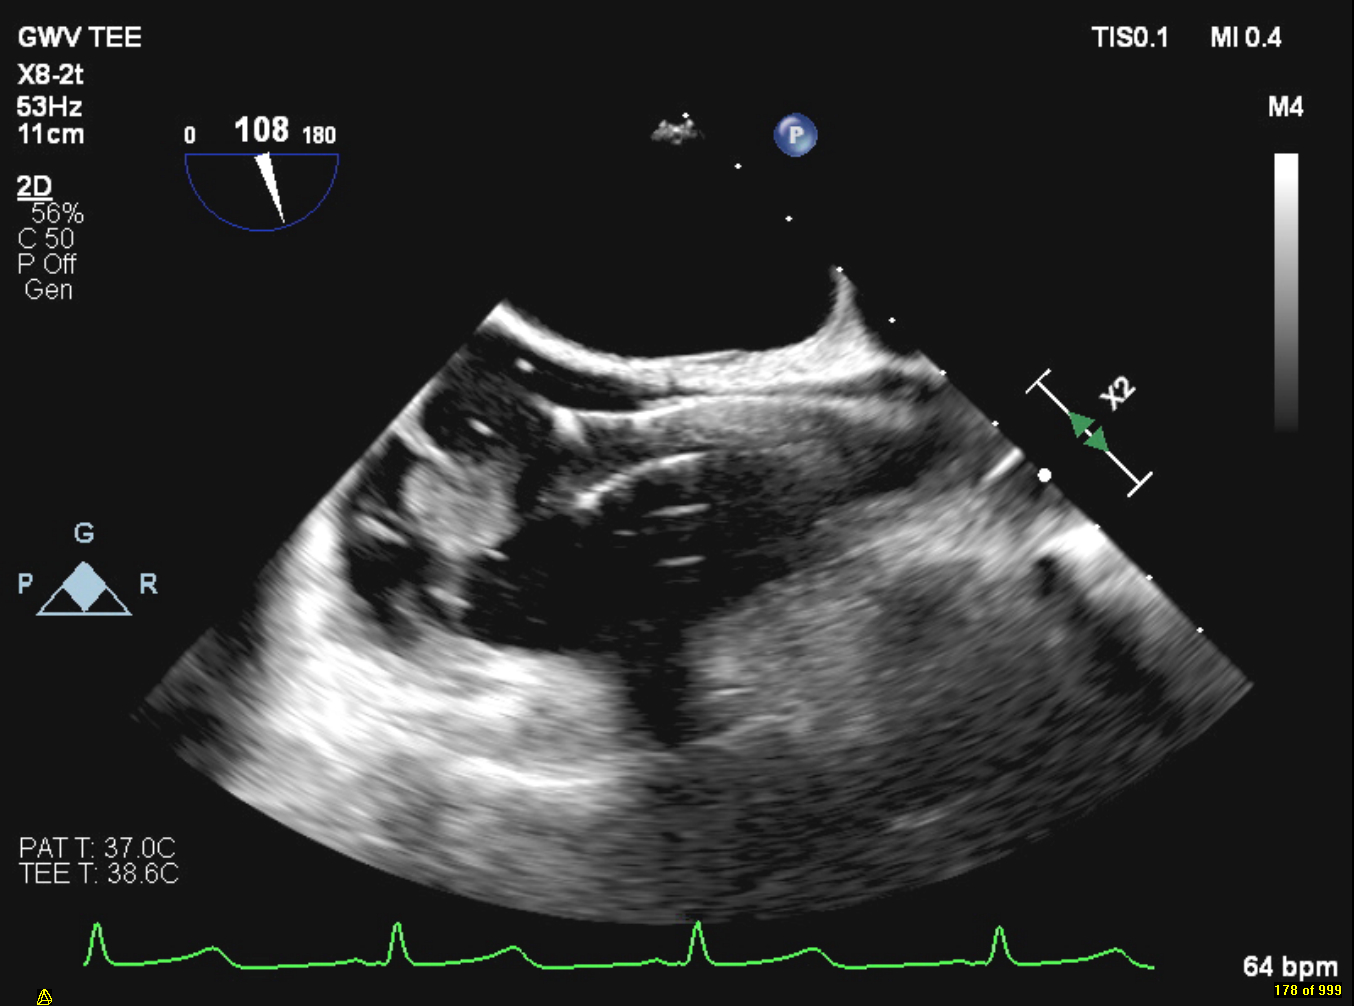

A 51-year-old female with ESRD on hemodialysis via a right tunneled catheter presented with fever and left knee pain. She was febrile and septic on admission; blood cultures grew MRSA. IV vancomycin was started, and the catheter was removed. Initial transthoracic echocardiography (TTE) showed no vegetations or intracardiac masses. CT chest post catheter removal revealed vegetations on the tricuspid valve, in the SVC, and right brachiocephalic vein with septic pulmonary emboli. Transesophageal echocardiography (TEE) showed a large, mobile, multilobular vegetation on the anterior tricuspid leaflet extending into the right atrium and SVC, with severe tricuspid regurgitation. She underwent transcatheter debulking with AngioVac, successfully removing vegetations from the tricuspid valve, SVC, brachiocephalic vein, and right heart. No residual vegetations were seen post-procedure. MRSA was also isolated from the left knee aspirate; she underwent incision and drainage. Blood cultures cleared following catheter removal and AngioVac intervention. She was discharged to a skilled nursing facility for rehabilitation and completed a six-week course of IV vancomycin.